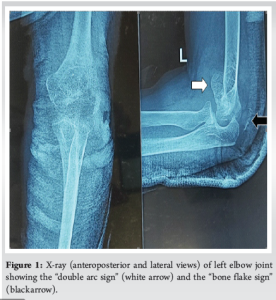

A woman in her late 40s, who is a homemaker by profession, visited the orthopedics outpatient department with complaints of pain, swelling, and an inability to move her left elbow (non-dominant limb) after experiencing an accidental fall onto an outstretched hand with the elbow joint in a semi-flexed position from a height of 2 feet. A clinical examination revealed swelling of the elbow, accompanied by significant tenderness on both the anterior and posterior sides of the elbow joint, as well as a severe limitation of motion at the elbow joint. The three-point bony relationship was preserved. There was a contusion at the tip of the olecranon in the area where the triceps muscle attaches, with no external skin breach, visible bony deformity, or neurovascular deficits. The patient reported no comorbidities or notable medical or surgical history in the past. The X-ray of the elbow joint (Fig. 1) revealed a double arc sign indicative of a capitellum fracture that extends to the trochlea, accompanied by a small bony fragment located proximal to the olecranon process, referred to as the “bone flake” sign, which suggests a DTTA fracture injury. A computed tomography (CT) scan with three-dimensional reconstructions (Fig. 2) validated the diagnosis of a variant of McKee type 4 [1,3] and Dubberley type 2A [8] capitellum fracture with extension to the trochlea, without any comminution or fragmentation, in addition to the DTTA fracture injury. This fracture pattern is distinctive because it has neither been classified nor described in existing literature. Before the surgery, written informed consent was obtained from the patient and her relatives (Figs. 1 and 2).